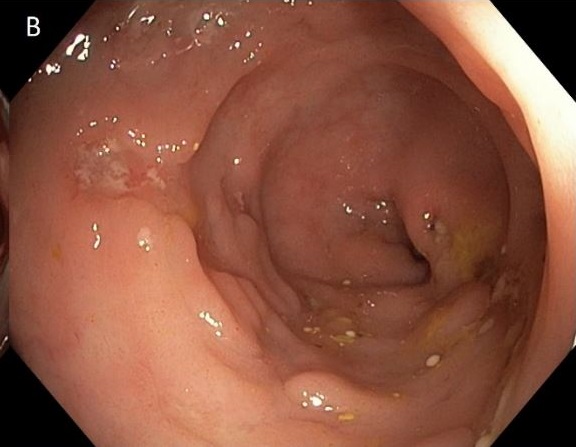

回盲弁の腫大(脂肪腫)と誤診される危険のある回盲弁上の濾胞性リンパ腫

こちらのサイトより引用させていただきました